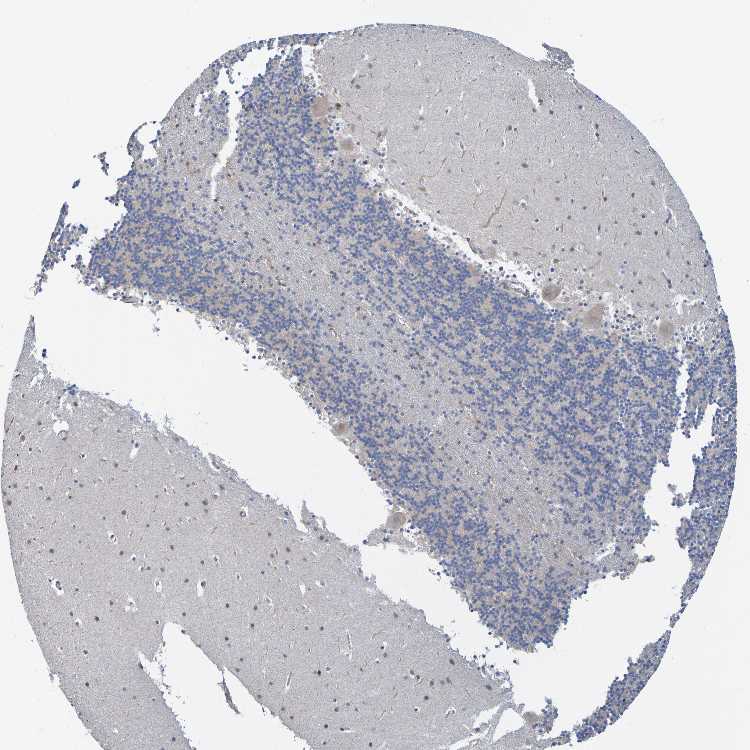

CEREBELLUM - Antibody stainingi

Antibody staining in the annotated cell types in the current human tissue is reported as not detected, low, medium, or high, based on conventional immunohistochemistry profiling in selected tissues. This score is based on the combination of the staining intensity and fraction of stained cells.

Each image is clickable and will lead to virtual microscopy that enables deeper exploration of all samples and also displays staining intensity scores, fraction scores and subcellular localization as well as patient and tissue information for each sample.

Antibody HPA011949

Purkinje cells Not detected

Cells in granular layer Not detected

Cells in molecular layer Not detected